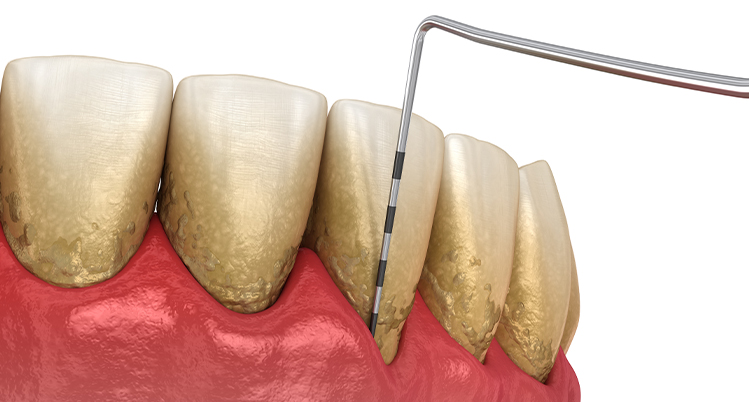

- 歯周ポケットの深さを一本ずつ全周に渡り測定し、異常な深さの部位がないかどうか検査します。

- 歯周ポケットを触れた際に出血している部位がないか確認します。出血は炎症が存在するサインとなります。

スケーリング

スケーリングとは

歯肉の上のプラーク、歯石を特殊な機械をもちいて除去することをいいます。

スケーリングで歯石を除去する重要性

歯石は硬く歯面や歯根に強固に付着しているため、ブラッシングで除去することはできませんが、細菌が増殖する場となります。つまり歯石が付着している状態では、そこから細菌が毒素を産生しさらに歯周病を進行させてします。この悪循環を止めるために、歯科医院で歯石を除去し、さらには歯石が付着しにくい状態を維持する必要があります。